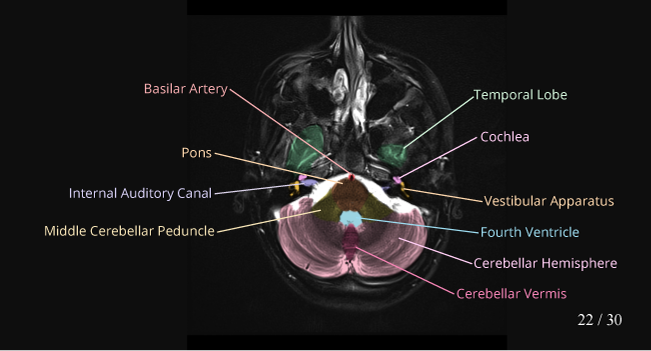

Cerebellum Anatomy Mri

MRI Basics